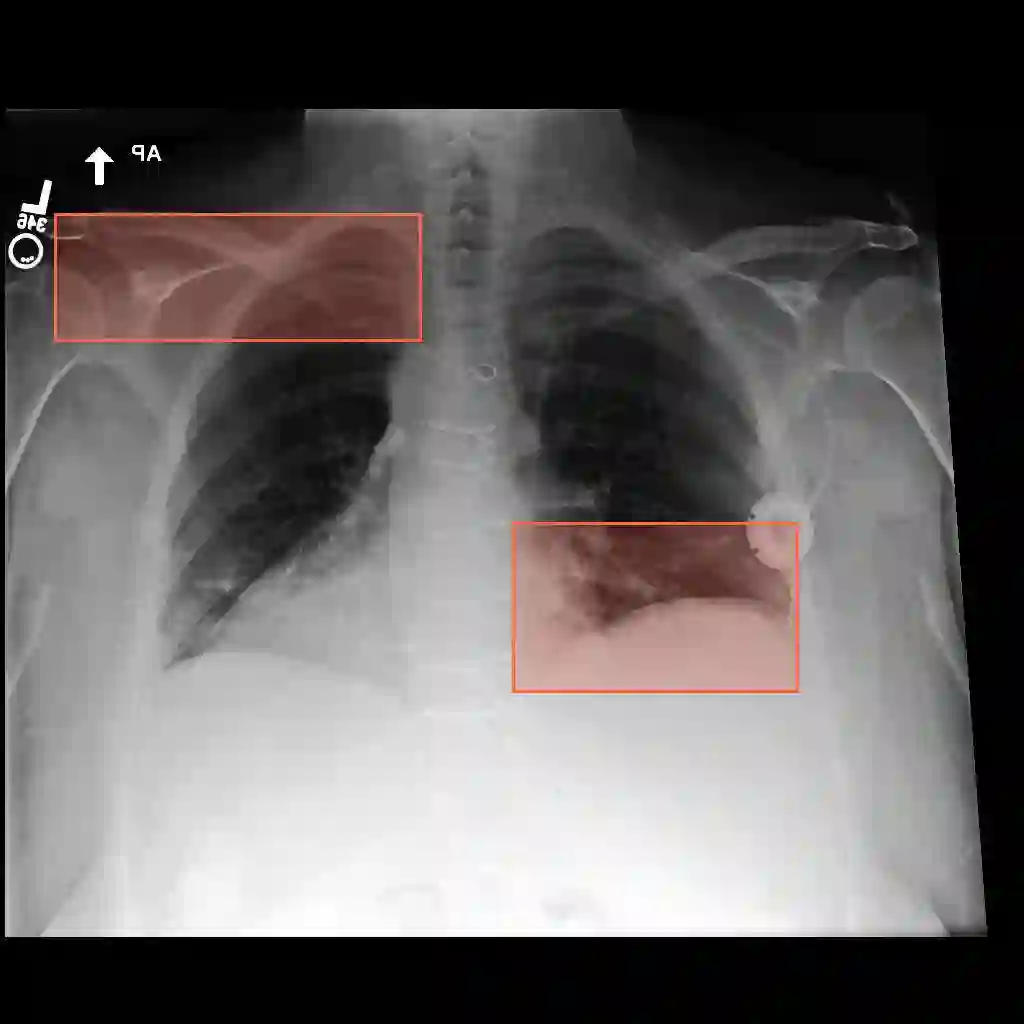

Multimodal medical large language models have shown impressive progress in chest X-ray interpretation but continue to face challenges in spatial reasoning and anatomical understanding. Although existing grounding techniques improve overall performance, they often fail to establish a true anatomical correspondence, resulting in incorrect anatomical understanding in the medical domain. To address this gap, we introduce AnatomiX, a multitask multimodal large language model explicitly designed for anatomically grounded chest X-ray interpretation. Inspired by the radiological workflow, AnatomiX adopts a two stage approach: first, it identifies anatomical structures and extracts their features, and then leverages a large language model to perform diverse downstream tasks such as phrase grounding, report generation, visual question answering, and image understanding. Extensive experiments across multiple benchmarks demonstrate that AnatomiX achieves superior anatomical reasoning and delivers over 25% improvement in performance on anatomy grounding, phrase grounding, grounded diagnosis and grounded captioning tasks compared to existing approaches. Code and pretrained model are available at https://github.com/aneesurhashmi/anatomix